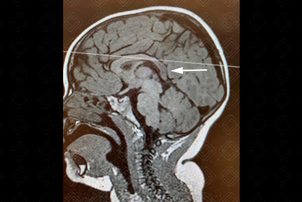

Texto alternativo para a imagem Crédito: Dra. Elazir Mota - Rio de Janeiro/RJ

Descrição da imagem: Sagital T1, comprometimento do esplênio do corpo caloso (seta branca).

• Achados precoces: Redução do sinal em T1 na substância branca profunda; no T2 há um hipersinal confluente periventricular (em forma de borboleta), com preservação de mielina perivenular (padrão tigroide) e, inicialmente, pode haver preservação das fibras em U;

• Achados tardios: Atrofia cerebral. Na ressonância observa-se o envolvimento das fibras em U, corpo caloso e cápsula interna.